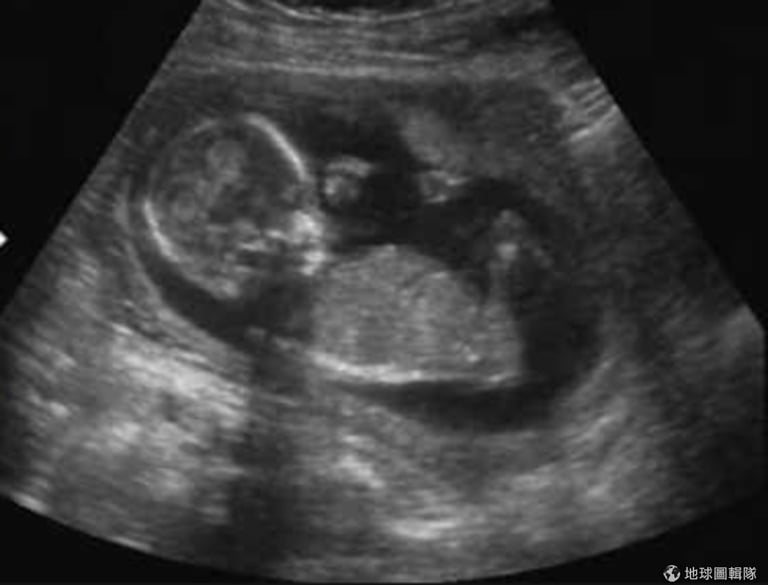

這是我第一眼看到我的女兒。

第一眼在超音波上見到她,她是怪物的小孩,卻是個天使

當第一眼看到她時,是在墮胎婦產科裡的超音波影像中,我存了好幾個月的錢才去成的,在努力存錢的這幾個月間,我也自我調適心情,準備面對即將席捲而來的兩種感覺。

最後,我終於看到超音波影像。這天距離我被強暴已經過了 17 週又三天了,過了好一段時間了,所以映入眼簾的不是當初那噁心的精蟲,我看到的是一個生命,是一個小孩,是我的嬰兒。

我啜泣的說:「我兩者都做不到,如果我留下孩子,我就要花下我的大半輩子養育一個禽獸的小孩,我無法看著小孩的眼睛,不想起我被強暴的事實。但如果我墮胎,我一定會大大的受傷一次,我會永遠忘不了我現在在超音波上看到的影像,我永遠都不會知道這小孩的未來可能會是多麽幸褔。」

超音波師把儀器再放回我的肚子上移動了一下,嬰兒的影像再度出現,不知道為什麼,在眼淚中我竟然不由自主地微笑了。

「我無法理解,這麼可惡又噁心的怪物,怎麼能創造出這麼美麗的生命?」我說出口。